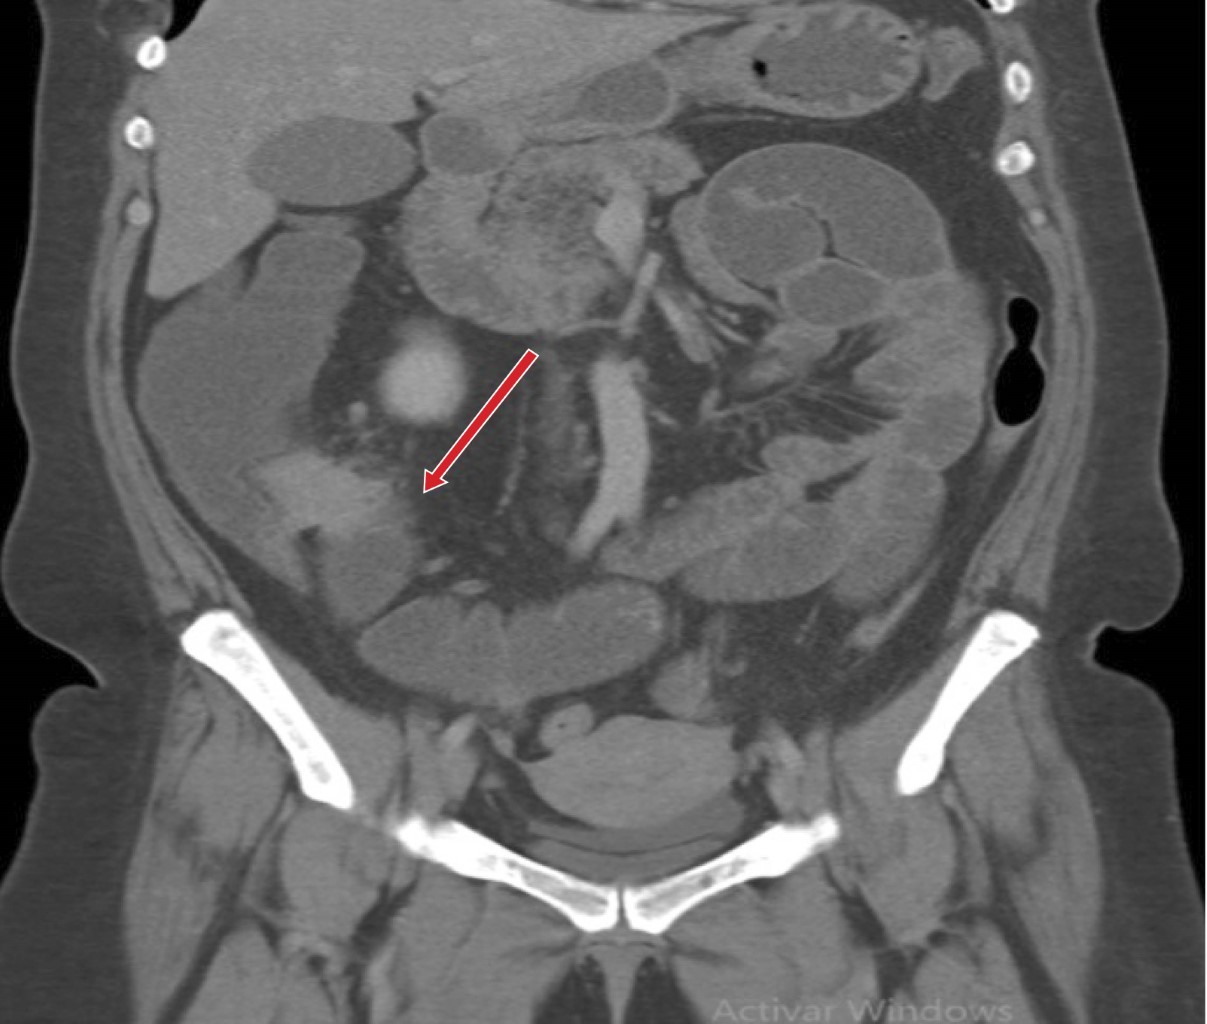

Se inició abordaje diagnóstico, se realizaron estudios de laboratorio y se obtuvieron cifras de leucocitos 9.08 × 103/mm3, hemoglobina 8.9 mg/dL, plaquetas 408 × 103/mm3, proteína C reactiva 42.4 mg/L. Se complementó el abordaje con estudios de gabinete, se inició con radiografías de abdomen, observando datos de oclusión intestinal tales como múltiples niveles hidroaéreos y ausencia de gas distal. Ante tales hallazgos, se decidió realizar tomografía de abdomen, la cual reportó obstrucción intestinal, sin descartar origen neoplásico con ganglios centinelas mesentéricos (Figuras 1 y 2).

Ingresó con diagnóstico de oclusión intestinal secundaria a tumoración en estudio, para realizar laparoscopía diagnóstica a proceder. Dentro de los hallazgos quirúrgicos se evidenció dilatación importante de asas de intestino delgado con zona de transición a nivel de íleon terminal, se observó una masa a nivel del mesenterio de íleon terminal (Figura 3A y B).

El diagnóstico preoperatorio es muy complicado. Los hallazgos por tomografía suelen ser muy inespecíficos, dentro de lo que se suele observar por este método de imagen son masas hipodensas con un realce periférico a la administración de medio de contraste, es imposible hacer un diagnóstico con certeza a menos que se identifique el pedículo vascular torcido en caso de una torsión. Mediante ultrasonido los hallazgos suelen ser una masa bien definida, hipoecoica y homogénea, y que mediante ultrasonido Doppler se confirma su estado avascular en caso de torsión, sin embargo, no se puede distinguir de un quiste. La resonancia magnética también es un método útil para el diagnóstico, pero poco utilizado debido al contexto de urgencia en el que se suele realizar el abordaje diagnóstico.4 Es de suma importancia ante la sospecha de un bazo accesorio la identificación del bazo principal previo a la resección del bazo accesorio. En nuestro caso se reporta por tomografía una masa sin lograr descartar patología neoplásica.